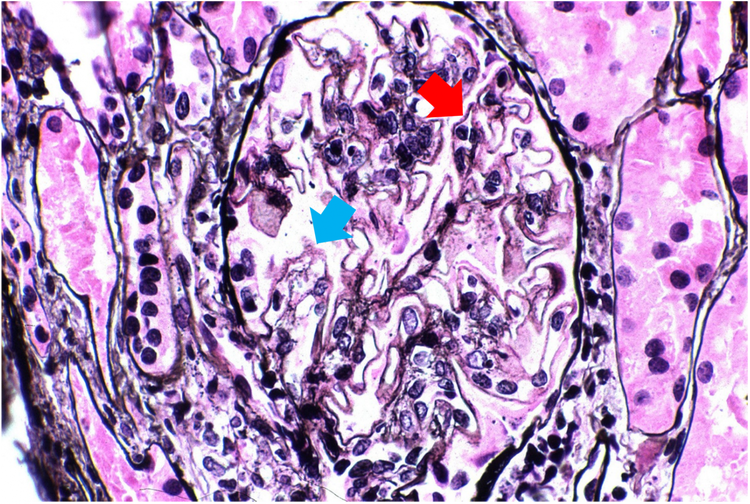

Abbildung 2 zeigt Proben von Patienten mit LN der Klasse V im fortgeschrittenen Stadium mit diffusen Löchern (blauer Pfeil) und kleine Ausbuchtungen (roter Pfeil) entlang der glomerulären Basalmembranen.3